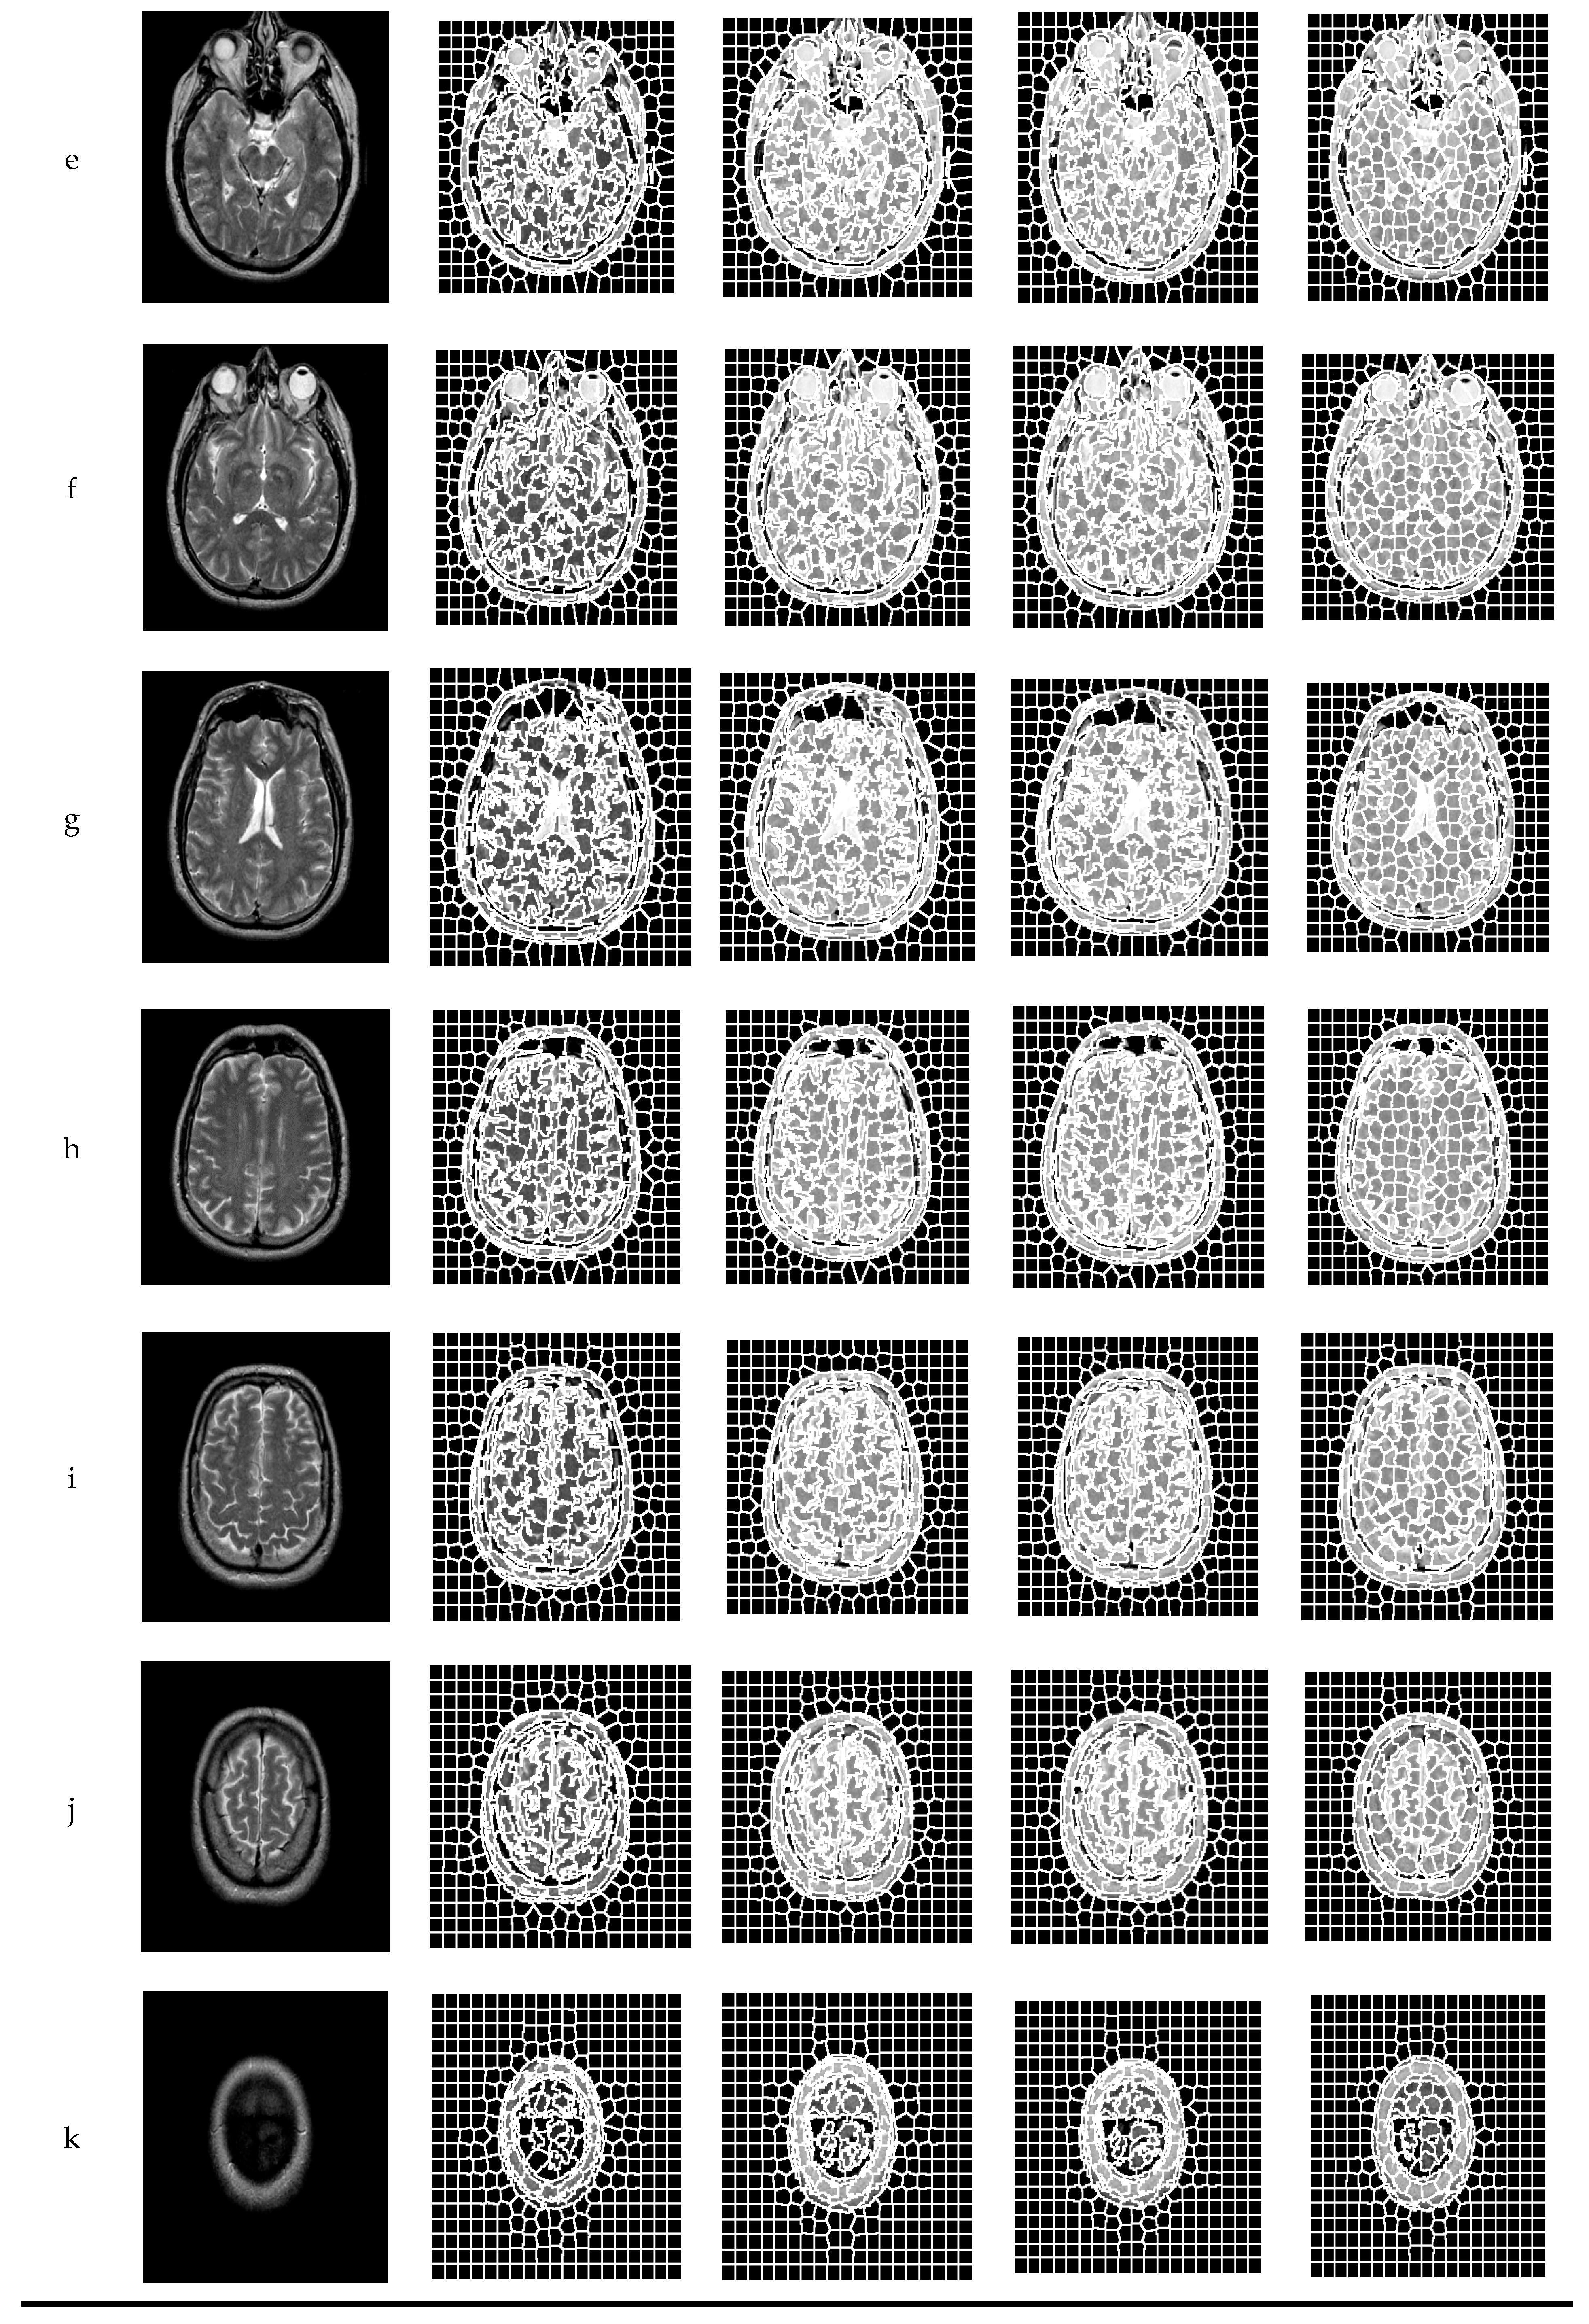

In order to verify the effectiveness of the proposed algorithm, experiments were carried out on several MRI brain images and were compared with traditional SLIC and enforced + SLIC algorithms. Figure 5 shows the segmentation results of traditional SLIC, enforced + SLIC, improved SLIC, and the proposed algorithm in this paper. As shown in Figure 5, after preprocessing, the target areas that are close to the color of the background area are segmented, the gray value consistency of the superpixel blocks is better, and the segmentation results are more accurate.

Figure 5.

The segmentation results of different algorithms.

Compared with SLIC, improved SLIC greatly improved the accuracy of superpixel segmentation and the consistency of superpixel blocks. As can be seen from Figure 5, after adding the local texture features of the image, the image features are better when calculating the similarity between pixels, and the pixels grouped into the same superpixel have more similar features. The superpixel edge of the proposed algorithm coincides with the edge of the target area in the image. The target areas close to the gray value of the background area and the smaller target areas that are misclassified are also significantly reduced. The superpixel blocks are more uniform and regular, and the accuracy of superpixel segmentation and the consistency in the superpixels are further improved in the proposed algorithm.